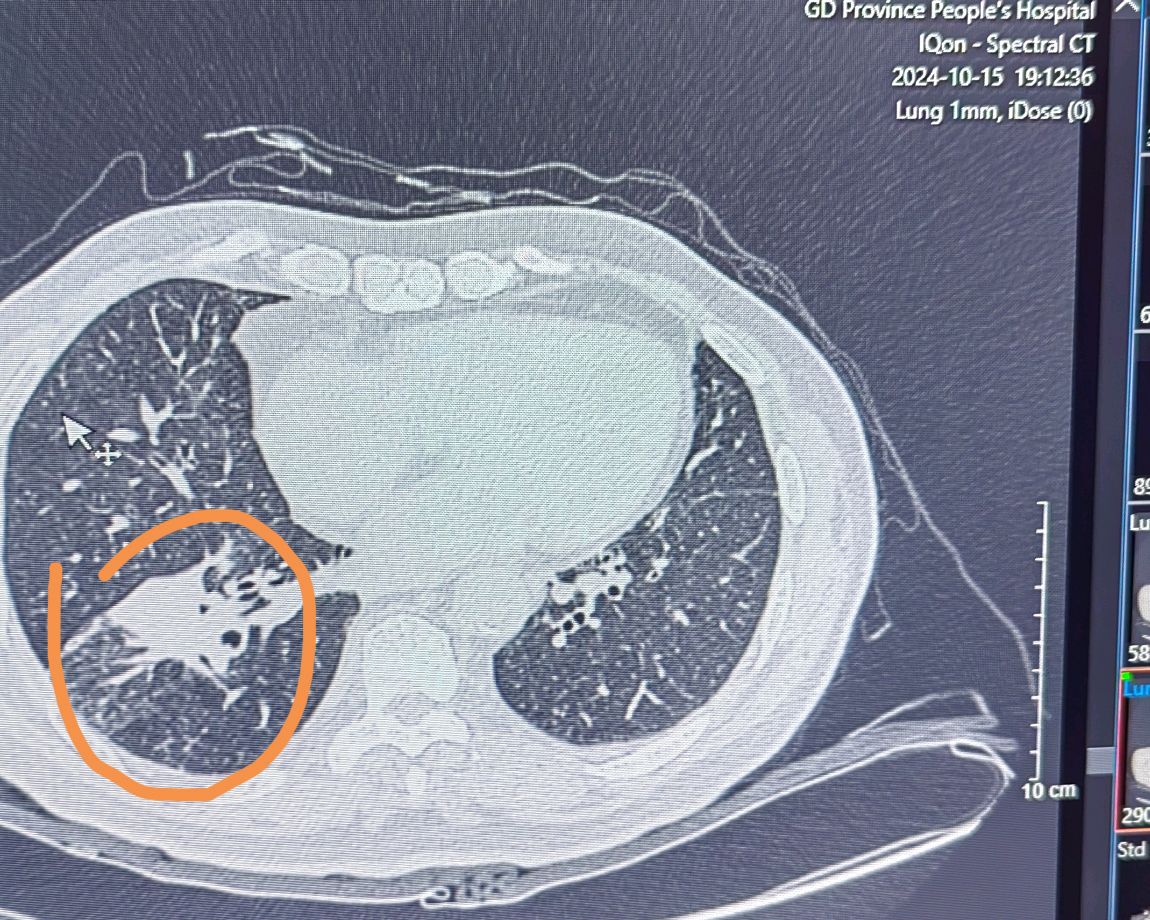

局部晚期肺癌经过化疗联合免疫治疗后一年手术

新辅助治疗后手术切除——中晚期肺癌患者的机遇